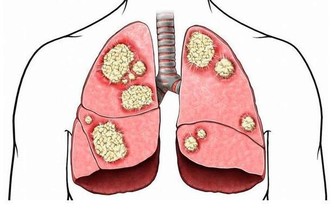

過量維生素K會導致人體出現癌症和長疹的現象。孕婦服用大劑量維生素K會造成新生兒黃疸。服用含維生素K量高的多種維生素亦影響口服抗凝劑的效果。